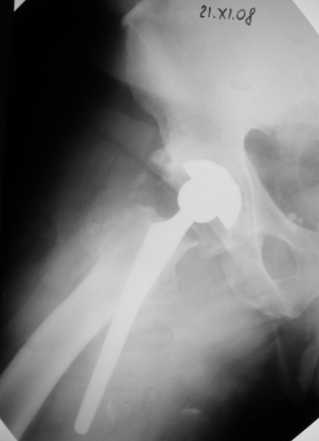

Больной Т. 56 лет, Диагноз: двухсторонний коксартроз 3-4 ст справа, 1-2 ст слева 2.10.08 выполнена операция тотальное бесцементное эндопротезирование. Использовался наружный доступ, положение на боку. Операция протекала без особенностей.

Выполнен послеоперационный ренгеноконтроль в прямой проекции. Рана зажила.

Уважаемый Глеб, предложенные снимки впечатлили! Никто не застрахован...